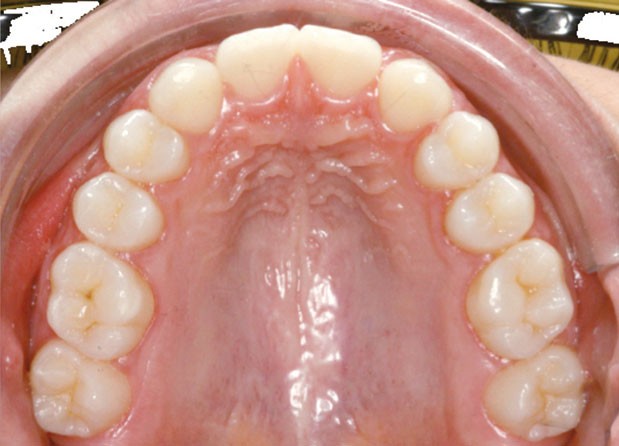

Les vues endo-buccales après extraction de 52 montrent des relations occlusales de classe II, un léger encombrement incisif mandibulaire et une tendance à la fermeture spontanée des espaces des incisives latérales confirmant le choix thérapeutique d’une fermeture d’espace (fig. 2).